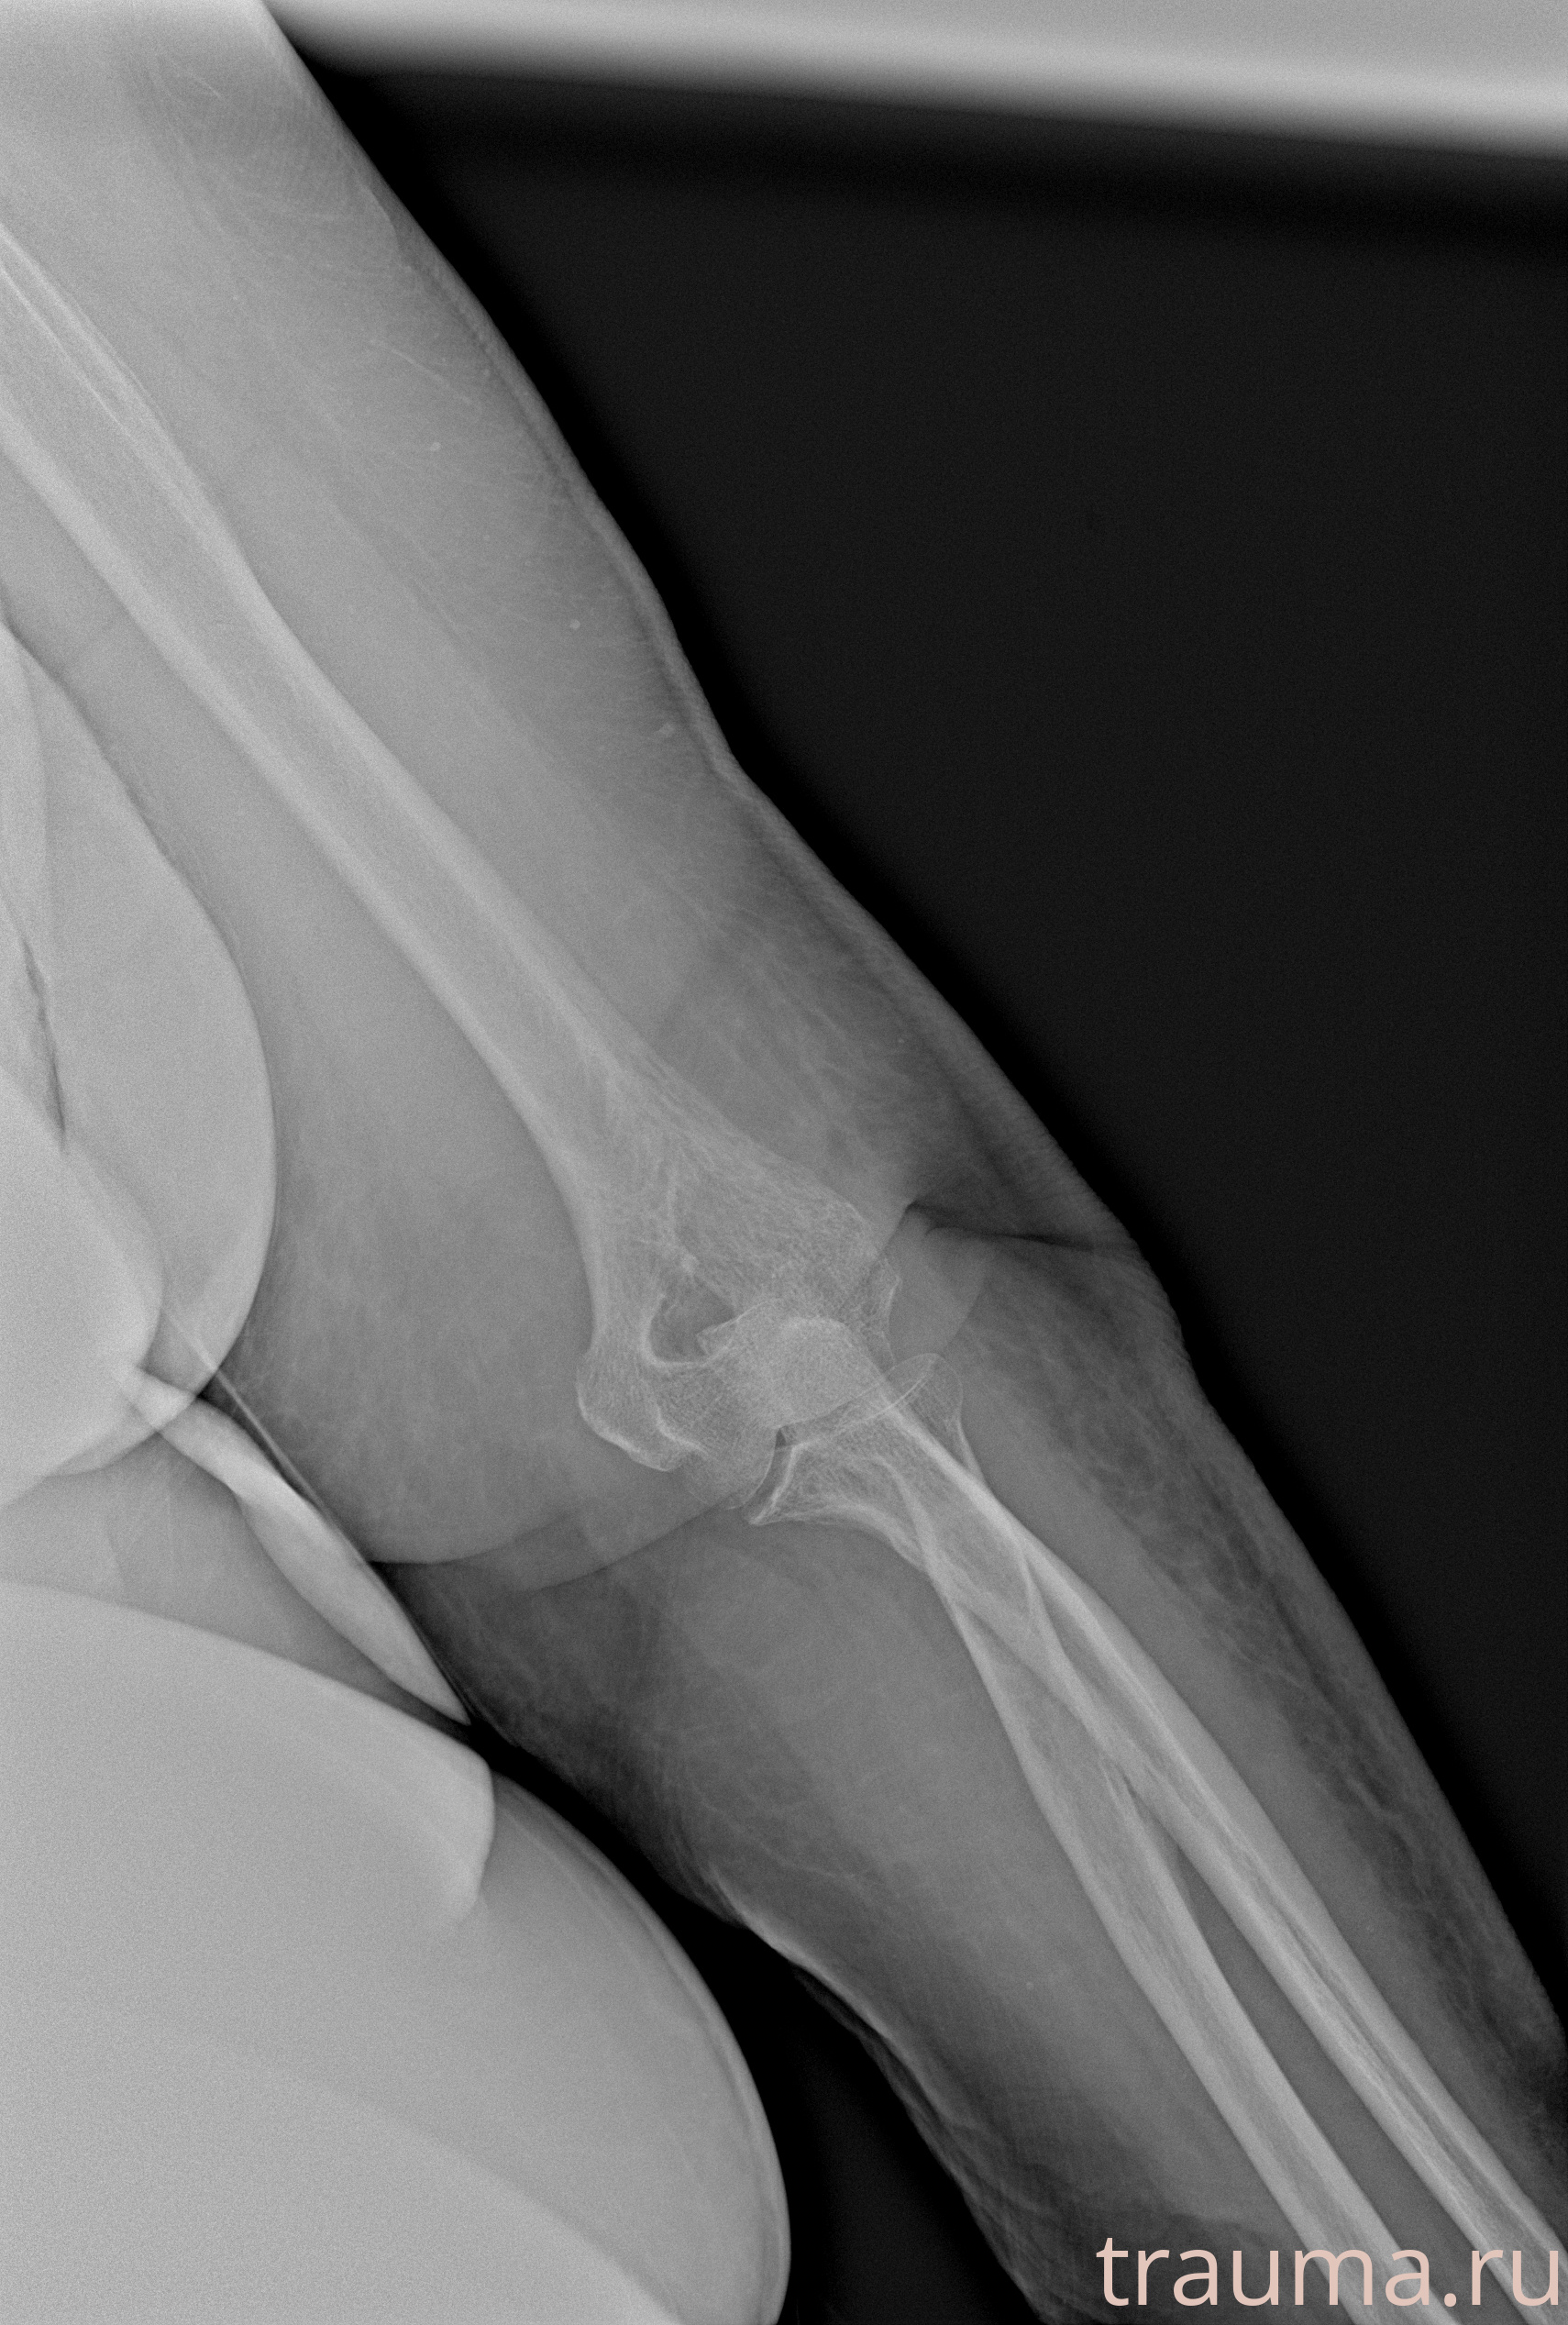

Рентгенограммы

Рентген на дому: по вашему адресу приезжает врач-рентгенолог, травматолог-ортопед с мобильным рентгеновским аппаратом, проводит диагностику травмы или заболевания, делает необходимые рентгенограммы, дает рекомендации по дальнейшему лечению. Получить качественные снимки в домашних условиях возможно благодаря уникальной методике, разработанной МосРентген Центром для института  Склифосовского